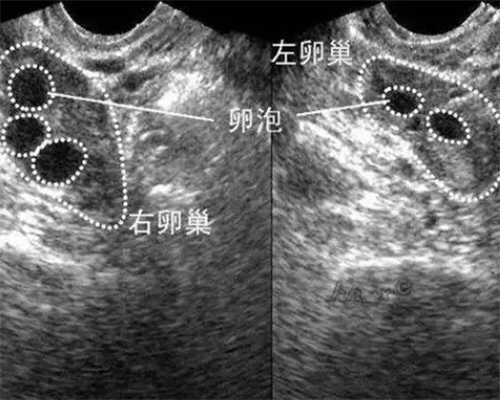

沈阳202 医院的于月新专家做试管婴儿也很不错,她是生殖医学科主任、教授、硕士研究生导师,从事妇产科临床工作十余年,擅长生殖内分泌疾病及不孕不育症的治疗,尤其在辅助生殖技术方面有较深的造诣。尤其对高龄、卵巢功能衰退等疑难问题有丰富经验,并多年从事多囊卵巢综合征、闭经、月经失调等内分泌疾病的诊治。